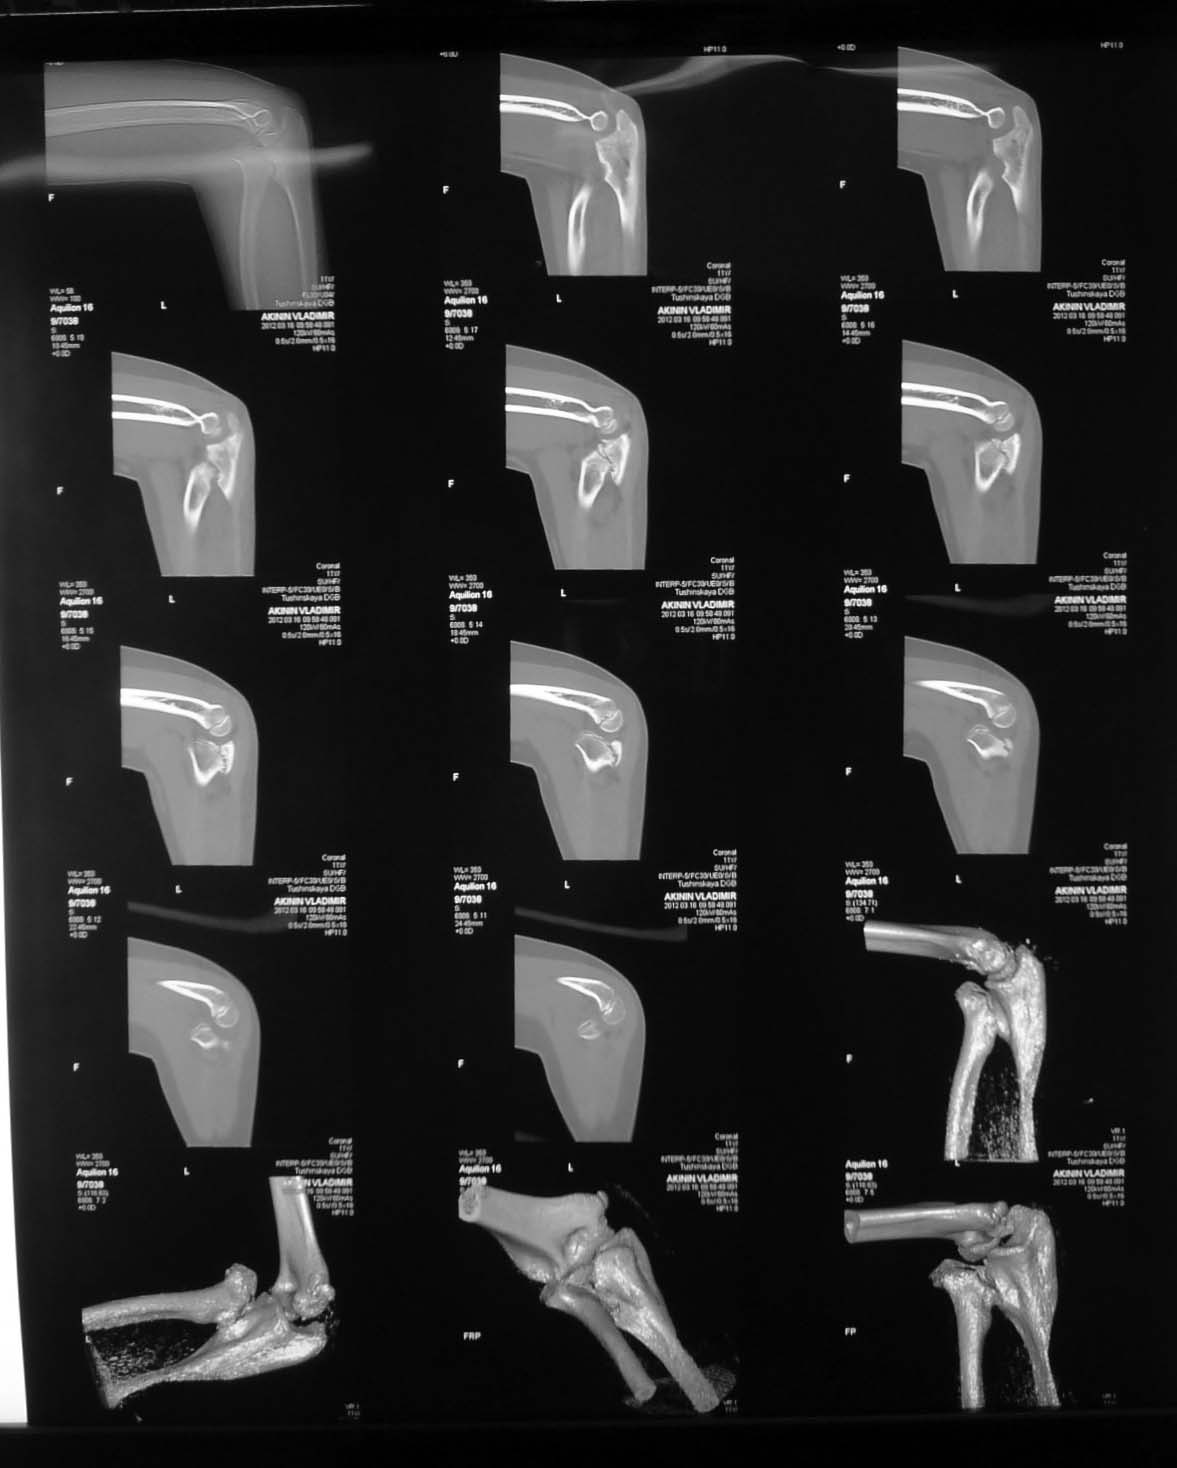

Уважаемый Тарас Рокита,

Обе большеберцовые кости имеют 2 вершины деформации, т.е. речь идет о двухуровневых корригирующих остеотомиях. И только после этого ставить вопрос об одномыщелковом протезировании. При тотальном протезировании, возможно, можно будет обойтись только диафизарными остеомиями

(дистальная CORA). К сожалению, точнее сказать не могу - для расчетов Рг низкого качества.